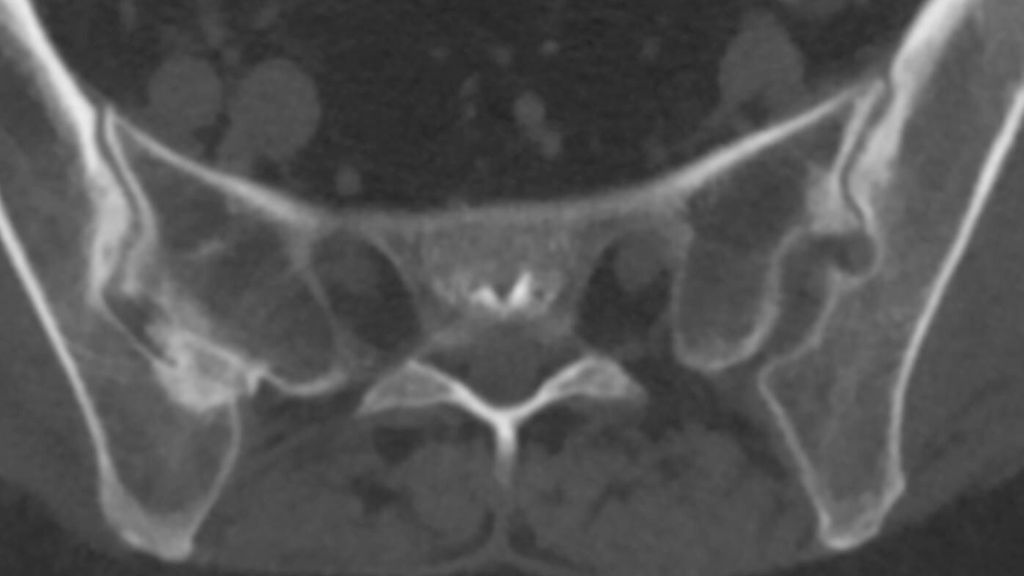

Abb. 2: Computertomografie: überlagerungsfreie CT-Darstellung der knöchernen Veränderungen an den Sakroiliakalgelenken mit Sklerosierungen, Erosionen und Ankylosen

Auch die CT hat als röntgenstrahlenbasiertes Verfahren ihre Stärke im Bereich der knöchernen Strukturen, mit dem Vorteil einer überlagerungsfreien Darstellung (Abb. 2). Die Auflösung ist für die meisten Fragestellungen ausreichend, erreicht jedoch nicht das Niveau von Röntgen-Detailaufnahmen oder hochauflösenden Ultraschalluntersuchungen. Die CT ist prinzipiell auch für großräumige Untersuchungen geeignet, wobei die erhebliche Strahlenbelastung als limitierender Faktor zu bedenken ist. Die Verfügbarkeit ist allgemein gut, und die Untersuchungsdauer ist kurz. Allerdings ist eine CT mit einem gewissen geräte- und untersuchungstechnischen Aufwand verbunden und dementsprechend teuer.